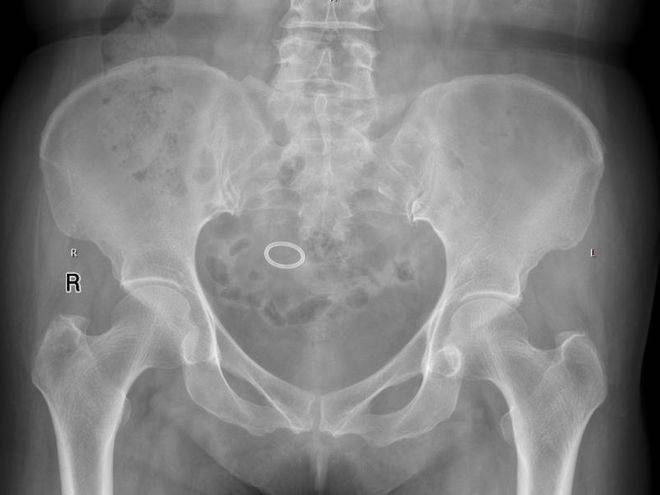

入院后很快安排了骨盆平片,也就是给环和骨盆照了个照片。发现是个圆环,这还是上个世纪80、90年代最常用的那种“O”形环,没有尾丝,不好取,且取的时候很容易断裂、残留。